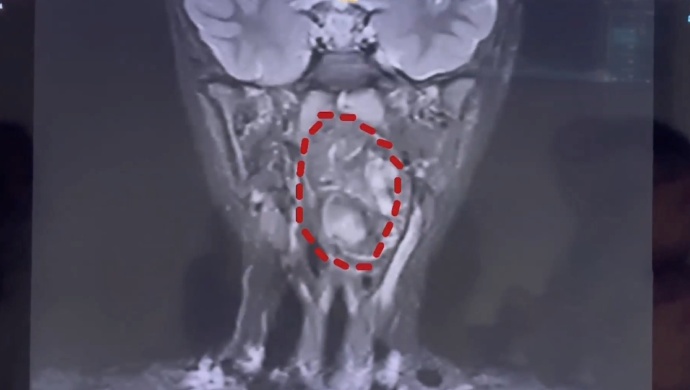

慌乱中,母子俩前往复旦大学附属儿科医院就诊。经该院耳鼻咽喉头颈外科副主任陈超诊断,这枚肿瘤是由生殖细胞长成的畸胎瘤,“我们可以看出它有脂肪,有软骨,这是一对双胞胎,一个是正常发育成的人,另外一个可能残留在这个咽旁间隙里面,就发育成了这样的一个畸胎瘤。”

检查显示,小亮的口咽腔仅8厘米左右,而6.6×3.5×3厘米的肿瘤已占据大部分气道,仅留一条缝隙透气,若不及时手术,可能导致呼吸道梗阻窒息。更棘手的是,肿瘤紧贴颈内颈动脉,手术出血风险极高。